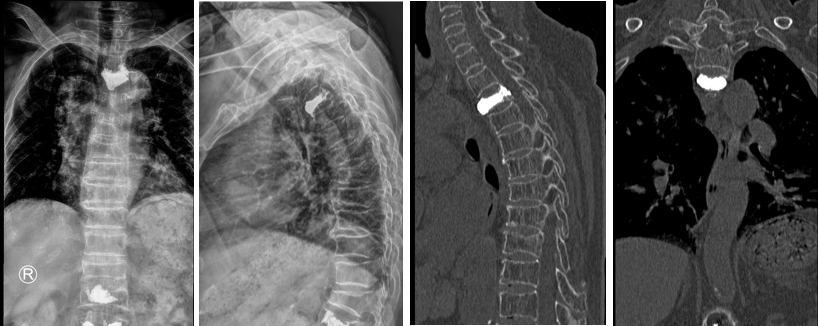

丁老太入院第三天,姜主任在骨科主治医师蒋伟刚的配合下,成功为其实施了机器人辅助下经皮椎体球囊扩张成形术。术后第一天,患者可以下地活动,疼痛消失;第二天即出院,整个住院时间仅6天,真正做到了术后快速康复!丁老太的女儿感慨道,庆幸有独墅湖医院骨科姜主任和他的团队的出手相助,再加上手术机器人辅助,才帮助老人家过了这一关!

椎体强化术是治疗骨松性椎体压缩性骨折的有效手术方法,其中使用最多的是椎体后凸成型术,简称PKP术。随着科技的进步,过去通常无法实施的部位也可以施行该手术。手术效果立竿见影,这一技术使许多老年患者摆脱了难以忍受的痛苦,挽救了他们的生命。